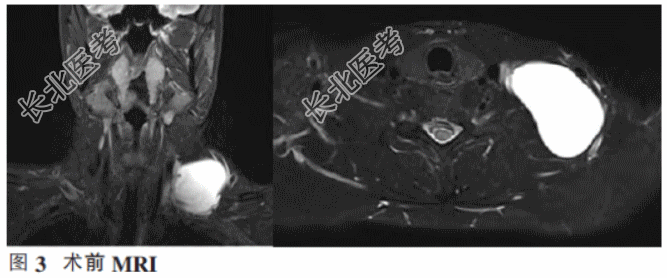

磁共振显示双侧颈部诸结构对称,左侧锁骨上区见较大局限性T1低T2高信号,边界清晰,病灶大小约5.7cm×5.5cm×4.8cm(前后、左右、上下)。增强扫描病灶边缘薄壁均匀强化,左侧颈总动脉及锁骨下动脉受压改变,左侧臂丛神经局部轻度受压、信号未见异常。双侧颈部Ⅱ区见增大淋巴结,较大者位于左侧颈部,直径约1.2cm,其余双颈各间隙结构清楚,未见颈部其他异常病灶影(图3)。初步诊断为左侧锁骨上囊性肿物。